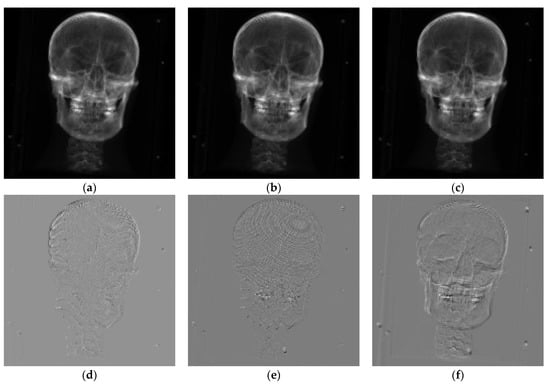

The results of the first group of experiments are shown in Figure 7. The second group of experimental results is shown in Figure 8, and the third group of experiments is shown in Figure 9. NCCS represents normalized cross-correlation based on the Sobel operator. NCCL represents normalized cross-correlation based on the LOG operator, and NCC represents normalized cross-correlation. Each result display chart is divided into two rows and three columns for comparative analysis of registration results. The first line represents the DRR image generated by CT projection after registration. The second line represents the difference between the reference image and the registered DRR image. The first column corresponds to the normalized cross-correlation based on the Sobel operator from top to bottom. The second column corresponds to the normalized cross-correlation based on the LOG operator. The third column corresponds to the original normalized cross-correlation. The different images of the three experiments show that the difference image is the smoothest when NCC based on the LOG operator is used as the similarity measure. The difference between the registration result and the reference image is the smallest; NCC’s registration effect based on the Sobel operator is the second. The difference between the original NCC algorithm and the reference image is the largest. The NCC based on the LOG operator is the largest. The registration results are similar to those obtained by NCC based on the Sobel operator.

Figure 7. Experimental results of group 1. (a) DRR based on NCCS registration; (b) DRR after NCCL registration; (c) DRR based on NCC registration; (d) difference map after registration based on NCCS; (e) difference map after registration based on NCCL; (f) difference map after registration based on NCC.

Figure 8. Experimental results of group 2. (a) DRR based on NCCS registration; (b) DRR based on NCCL registration; (c) DRR after registration based on NCC; (d) difference map after registration based on NCCS; (e) difference map after registration based on NCCL; (f) difference map after registration based on NCC.

Figure 9. Experimental results of group 3. (a) DRR based on NCCS registration; (b) DRR based on NCCL registration; (c) DRR after registration based on NCC; (d) difference map after registration based on NCCS; (e) difference map after registration based on NCCL; (f) difference map after registration based on NCC.